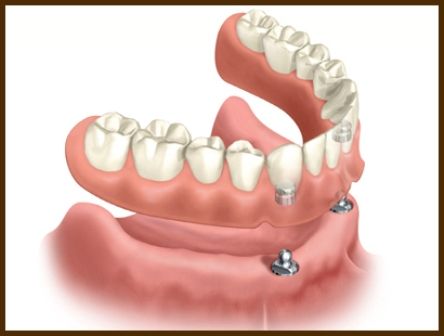

HANGİ DURUMLARDA İMPLANT YAPILIR? Total protezler artık dişsiz ağızların tek şansı olmaktan çıktı. Çene kemiğine yerleştirilen implantlar ve bunlardan destek alınarak hazırlanan protezler, artık hastalara kendi dişleriyle çiğniyormuş hissi vermekte ve bu sebeple sıklıkla tercih edilmektedir.

1) HANGİ DURUMLARDA İMPLANT YAPILIR? Tek diş eksikliğinin komşu sağlam dişlere dokunulmadan giderilmesinde, birden fazla diş eksikliğinin, takılıp çıkartılan protezler yerine, implantlar yardımı ile sabit köprüler yapılarak giderilmesinde, tam dişsizlik durumunda takılıp çıkartılan protezler (damak) yerine sabit protezler yapılabilmesinde, her türlü dişsizliğin ve eksik fonksiyonların giderilmesinde uygulanabilir.